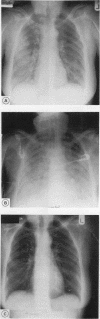

BACKGROUND: Low dose methotrexate has become established in the treatment of refractory rheumatoid arthritis. Until recently it has been considered that the use of a low dose regimen (< 20 mg/week) would avoid the pulmonary toxicity associated with the higher doses prescribed in malignant disease. Although initial experience with low dose methotrexate was encouraging, an increasing number of cases of an acute, life threatening pneumonitis are being reported in patients with refractory rheumatoid arthritis. PATIENTS: Since 1984 43 patients with refractory rheumatoid arthritis have been established on low dose methotrexate in the Oxford Health District. Five of these patients have subsequently developed acute methotrexate induced pneumonitis. The clinical and radiological features of these cases are described and previous reports reviewed. RESULTS: Five patients having low dose methotrexate treatment developed acute pneumonitis. Presentation was subacute and dominated by constitutional features. Respiratory symptoms developed insidiously but progressed rapidly with increasing dyspnoea associated with severe hypoxia. Chest radiographs were non-specific, showing diffuse interstitial infiltration and alveolar shadowing. Microbiological investigation gave negative results. In all cases methotrexate was discontinued and high dose corticosteroids started, with rapid clinical and radiological improvement. After withdrawal of steroid both clinical and radiological resolution was maintained at follow up. CONCLUSION: Acute pneumonitis is an uncommon but serious adverse effect of low dose methotrexate treatment for refractory rheumatoid arthritis. The initial presentation is non-specific and a high index of suspicion is required as respiratory failure may develop rapidly. Management depends on exclusion of infection, withdrawal of methotrexate, and high dose corticosteroid treatment. Full supportive treatment is indicated as the prognosis in such patients is good.